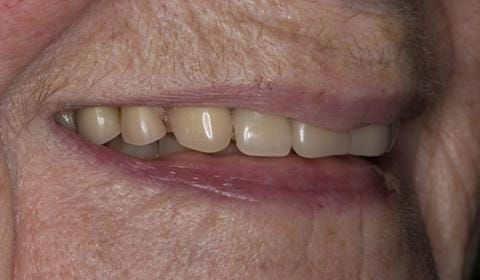

Following consultation and second discussion appointment the patient chose to have option 2 namely, a window denture - maxillary cobalt chromium based partial denture. The clinical situation and treatment process is shown in detail below with photographs. The patient was successfully rehabilitated with this and her quality of life considerably improved. The clinical work was provided by Finlay and the technical work by Rowan.